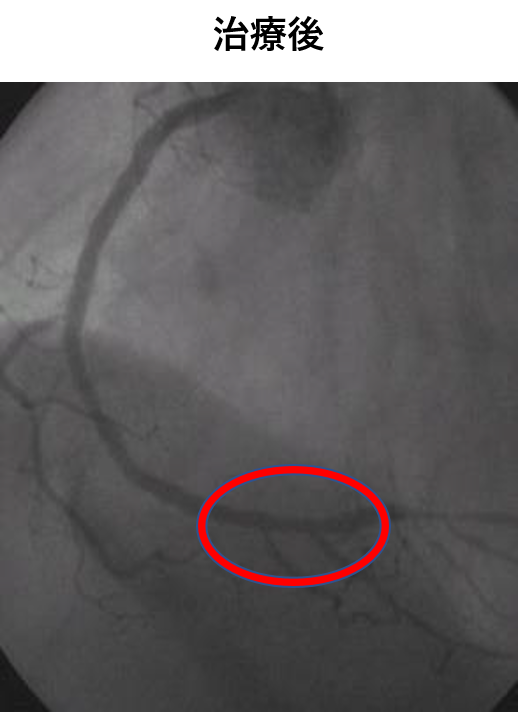

経皮的冠動脈インターベンション(PCI)は、脚の付け根や腕、手首などの血管から、カテーテルという医療用の細く柔らかいチューブを差し込んで、冠動脈の狭くなった部分を治療する方法です。

また、冠攣縮性狭心症の診断や、これまで診断がつかなかった微小循環障害による狭心症においても評価が可能です。

高度石灰化病変を伴う症例へのDebulkingデバイスを使用し、治療を行います。

急性冠症候群においては、救急搬送から再還流まで緊急対応が可能な体制を整えています。

お薬で症状や心電図の改善がない、または乏しい場合に心臓カテーテル検査を行い、高度な狭窄があれば、治療を行うことが一般的です。